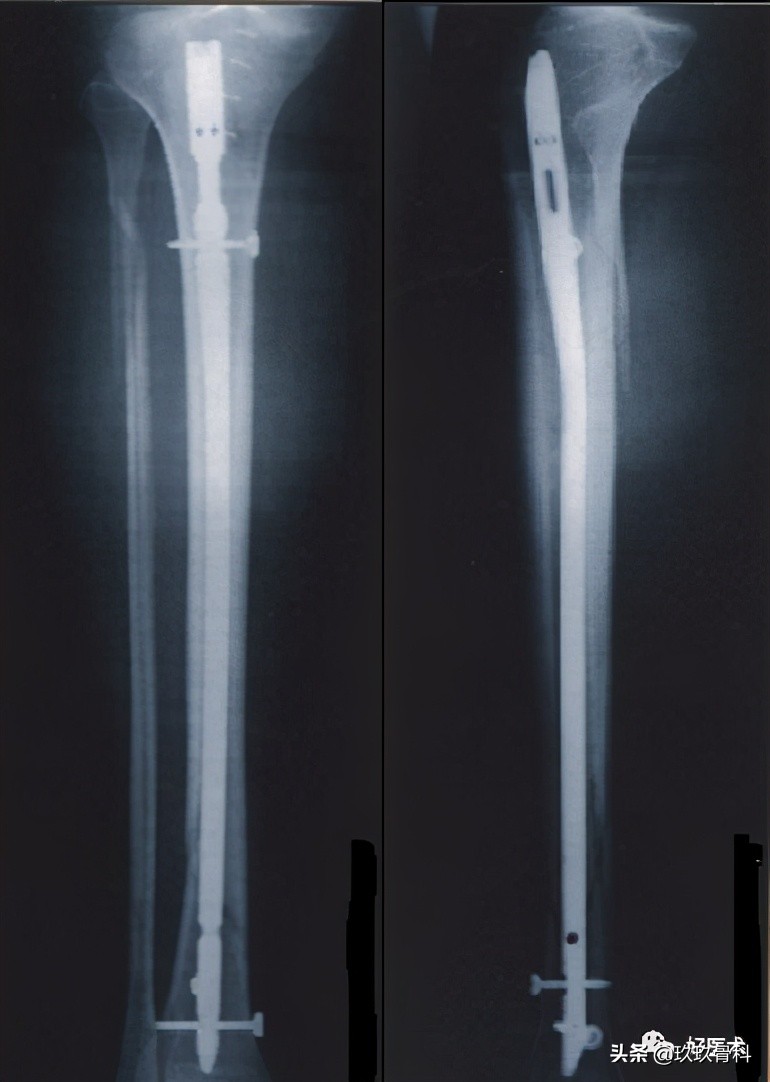

4.髓内钉插入技术

进针点入路

- 与髓腔纵轴在一直线上

- 毋太靠近进针点

- 长度适当:

--扩髓-长

--不扩髓-短

(进针点间接确认;不扩髓,不需要软组织保护)

股骨髓内钉插入技术

1)顺行股骨髓内钉进针点

部位:

- 梨状窝

- 梨状窝后外侧

2)顺行股骨髓内钉进针点的准备

胫骨髓内钉插入技术

1)顺行胫骨髓内钉进针点

- 在髓腔的中心线上

- 胫骨平台前缘

- 尽可能高

- 不损伤平台

2)顺行胫骨髓内钉进针点

- 最大限度屈膝

- 切口胫骨结节-髌骨下极沿髓腔方向

- 打开髓腔:导针与胫骨干纵轴矢状面呈15°

- 影像增强仪检查位置

(八)固定技术/交锁

交锁钉:

- 扩髓髓内钉→建议锁钉

- 非扩髓髓内钉→强制锁钉

稳定骨折:

- 动力方式锁定→轴向加压;防止旋转

远端锁钉:徒手或瞄准器技术

近端锁钉:瞄准器

锁钉数目:

远端≥ 2(股骨)或3(胫骨)枚